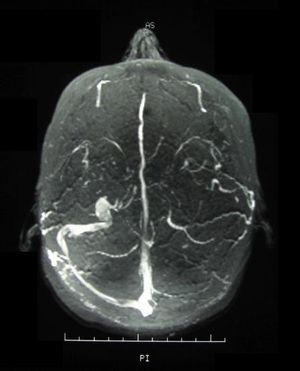

![]() | |